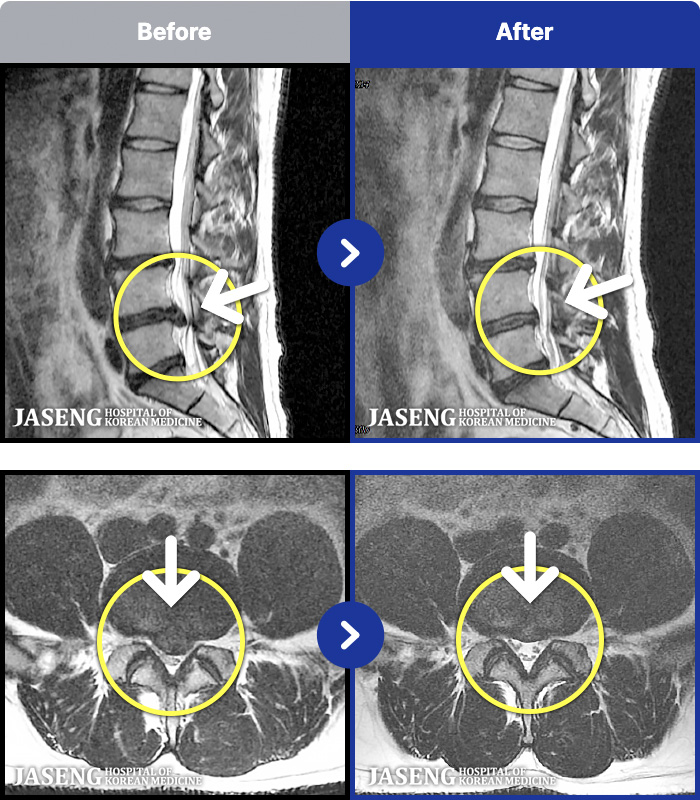

88 MRI ũ ʸ Ȯϼ.

ȯںп Ǹ ǿ ԿǾ, ο ġ ۿ Ƿ ġḦ Ͻñ ٶϴ.